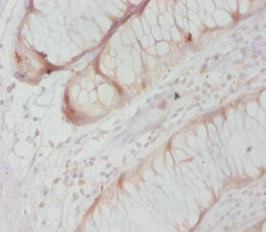

ApplicationELISA, WB, IHC, IF; Recommended dilution: WB:1:500-1:2000, IHC:1:10-1:100, IF:1:50-1:200